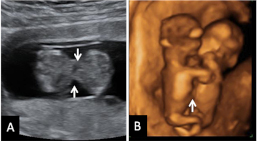

Ecografía en 3D de feto de 13 semanas con el cordón umbilical al cuello

La ecografía en tres dimensiones muestra un feto de 13 semanas de gestación con el cordón umbilical alrededor del cuello. En la imagen rotatoria se puede observar la situación del cordón, que sube por el tórax y que seguramente puede causar complicaciones en el embarazo.